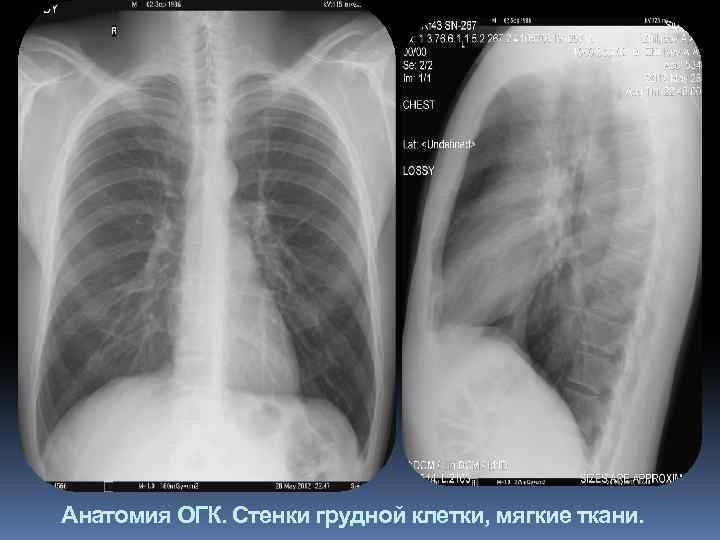

Грудные стенки. 1. Мягкие ткани. Видны в виде однородной тени по контуру в боковых отделах, передних и задних отделах (большая грудная мышца, тени грудиноключично-сосцевидных мышц, тени молочных желез, соски). 2. Элементы костного скелета грудной клетки (ребра, ключицы, грудина, позвонки, лопатки).

Анатомия ОГК. Стенки грудной клетки, ребра, позвоночник. мягкие ткани.

Мягкие ткани.

Анатомия ОГК. Стенки грудной клетки, мягкие ткани.